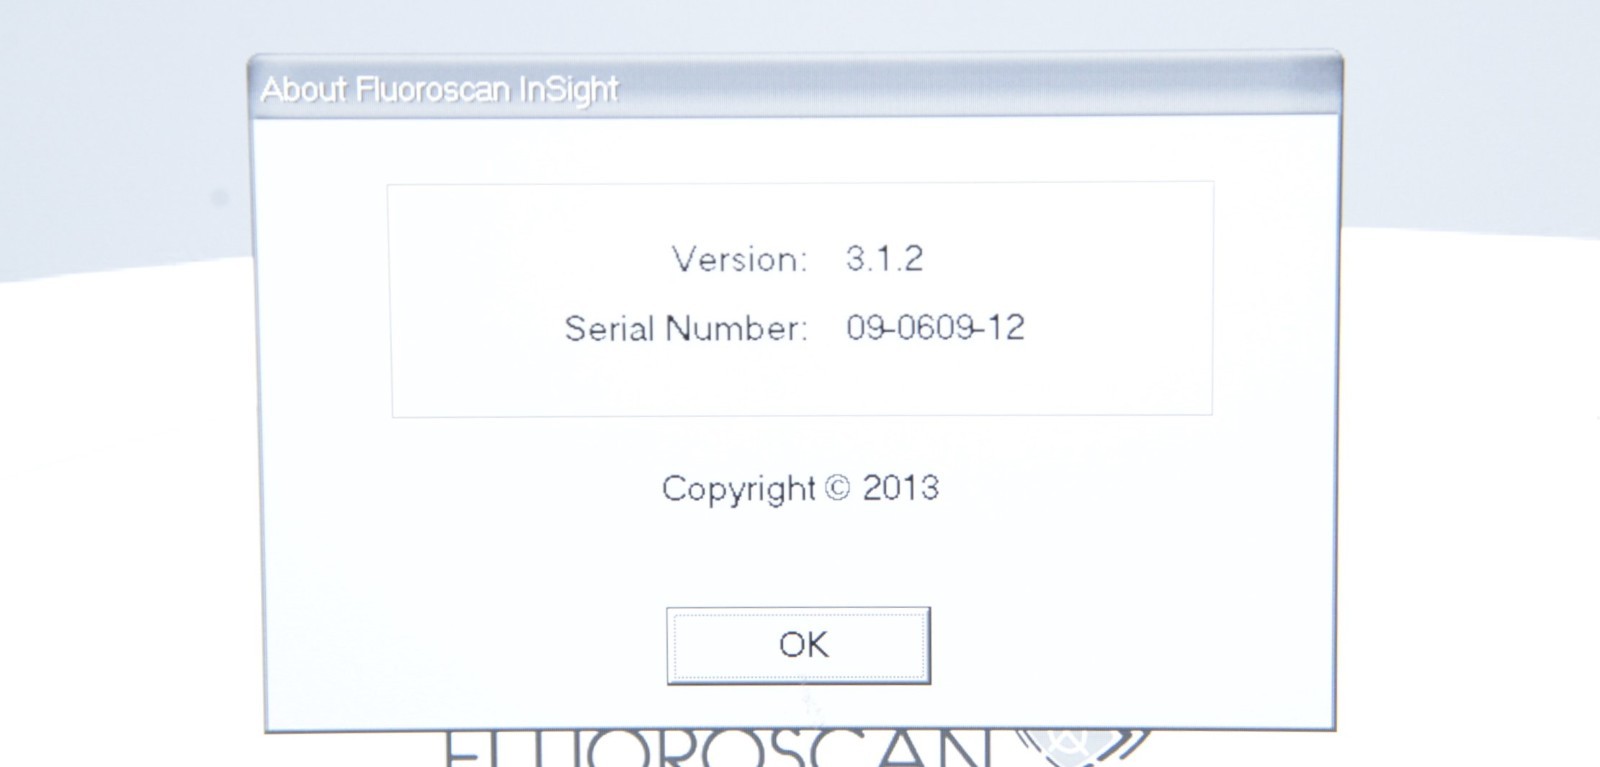

This Hologic Fluoroscan InSight 2 C-Arm X-Ray System 2009 W/ Wireless Footswitch is in good working condition. The system powers on properly. The display screen produces a clear image and all buttons respond properly to selection. All connection points are clean and in good condition. The arm adjusts properly. The images acquired is 21,892. There is a crack in the plastic casing. There are some scuff marks and chips in the paint from previous use (see photos). The screen has some scratches and the image intensifier cover is cracked. The D.O.M is June, 2009 and has Insight software version 3.1.2 installed. This unit comes with a 30 day satisfaction guarantee. Includes everything in the pictures and nothing else.